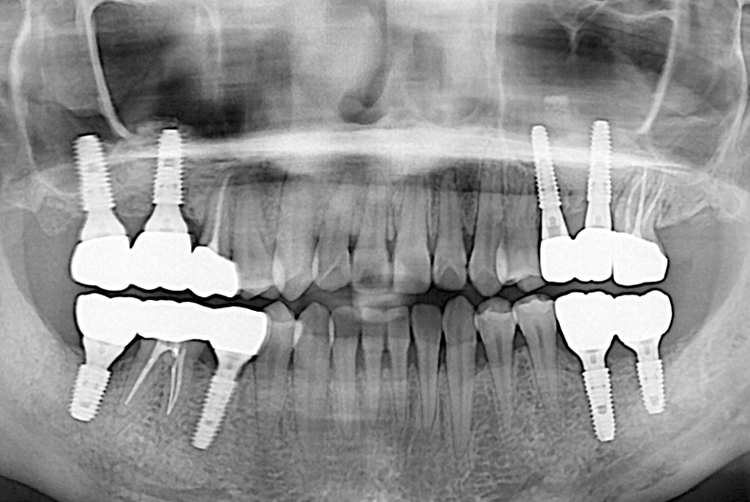

7cf8ead315147d1dd75f24443708e3e4.jpg

치료전 : 2018-01-10

523 신미란_후.jpg

치료후 : 2018-03-22

세종치과는 많은 환자와 다양한 케이스를 바탕으로 항상 편안한 임플란트 수술을 제공하고자 노력하고,

오래동안 튼튼히 쓸 수 있는 임플란트 수술을 가장 큰 목표로 삼고 있습니다